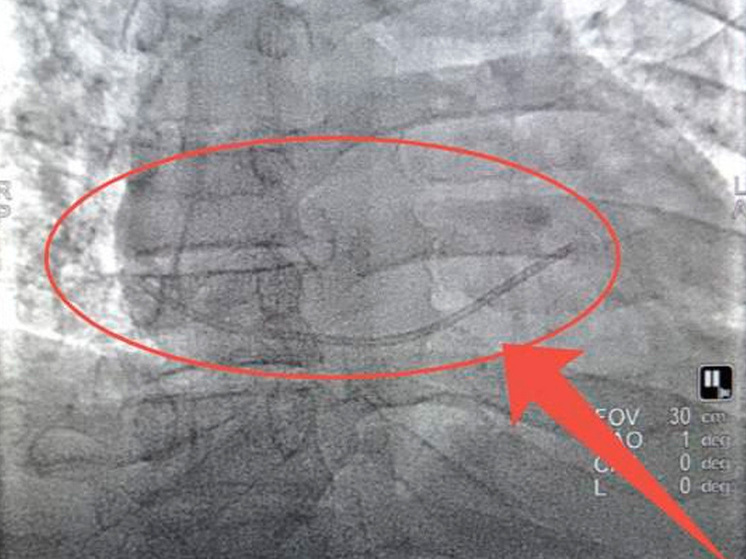

48-летний мужчина, страдающий тяжелым заболеванием поджелудочной железы, оказался на грани жизни и смерти после инцидента в реанимации одной из больниц Липецка. Во время его лечения катетер оторвался, и его обломок был смещен током крови в правый желудочек сердца.

В экстренном порядке пациента доставили в Липецкую областную больницу, где команда врачей под руководством кардиохирурга Алексея Литвиненко провела малоинвазивную операцию.

Благодаря высокому уровню профессионализма медиков, удалось избежать вскрытия грудной клетки: катетер был успешно извлечен через сосуд. Сейчас состояние пациента стабилизировалось, и он находится под наблюдением врачей.